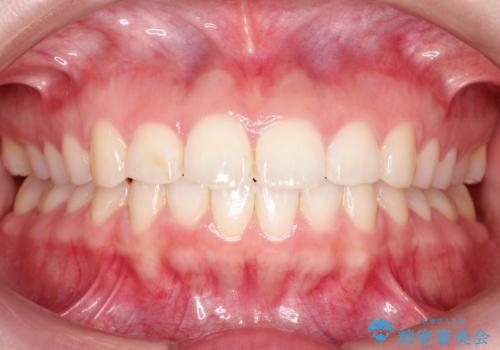

【インビザライン】前歯が出ているのを治したい

- 前歯が出ていることを主訴に来院されました。

前歯の突出感が改善され、満足していただきました。